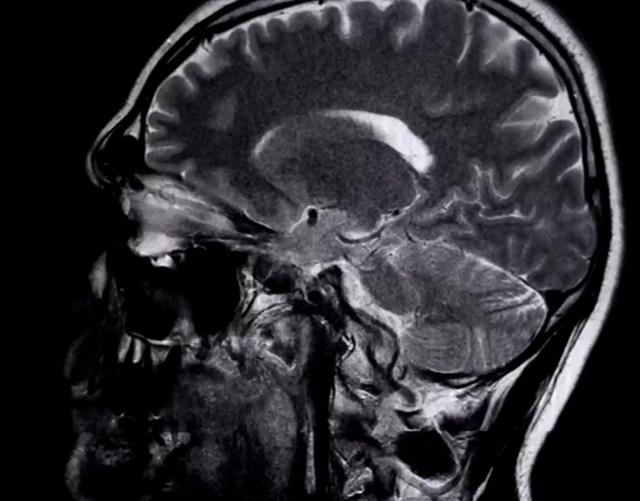

使用仪器观测的人脑图像

大学时,康纳有几次脑震荡的经历,“硬件”受伤后“软件”的运行方式也发生了变化,这让他开始关注大脑和意念之间的关系。一次,他听说了一个开源(指任何人都可以查看、修改和增强其源代码)软件,可低成本地创建较为简单的脑电图(高等脊椎动物大脑皮层的神经组织经常出现一种持续的、自发性的电位变化,使用电子技术引导、放大、记录这种脑电位变化所呈现的波形图)系统。经过一段时间的研究,康纳在屏幕上看到了自己的脑电波,这个瞬间改变了他的人生。